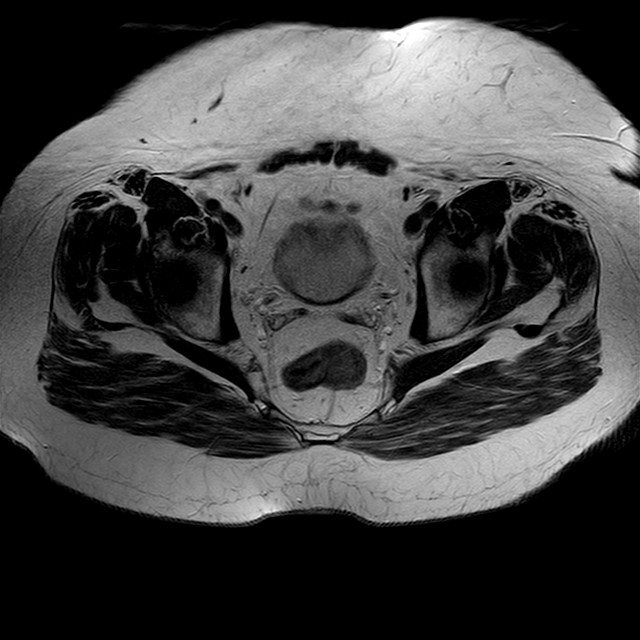

eT2w TSE

Evidenti e simmetriche alterazioni osteofitosiche in regione coxo femorale con riduzione delle rime articolari. Degenerazione completa del cercine glenoideo. Non attuali segni di versamento articolare. Non segni di edema osseo che escludono attuale algodistrofia od osteonecrosi. Lieve e simmetrica riduzione del trofismo della muscolatura glutea.